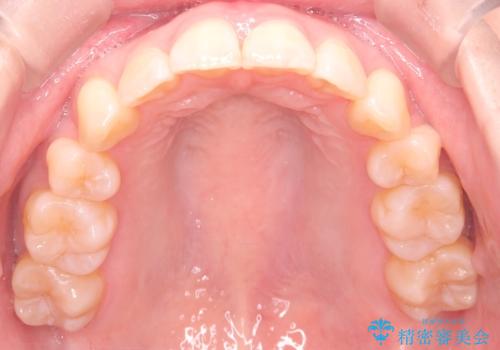

来院が途中途絶えたこともあり、4年ぐらい期間がかかりましたが、インビザラインだけで治療を終えることができました。